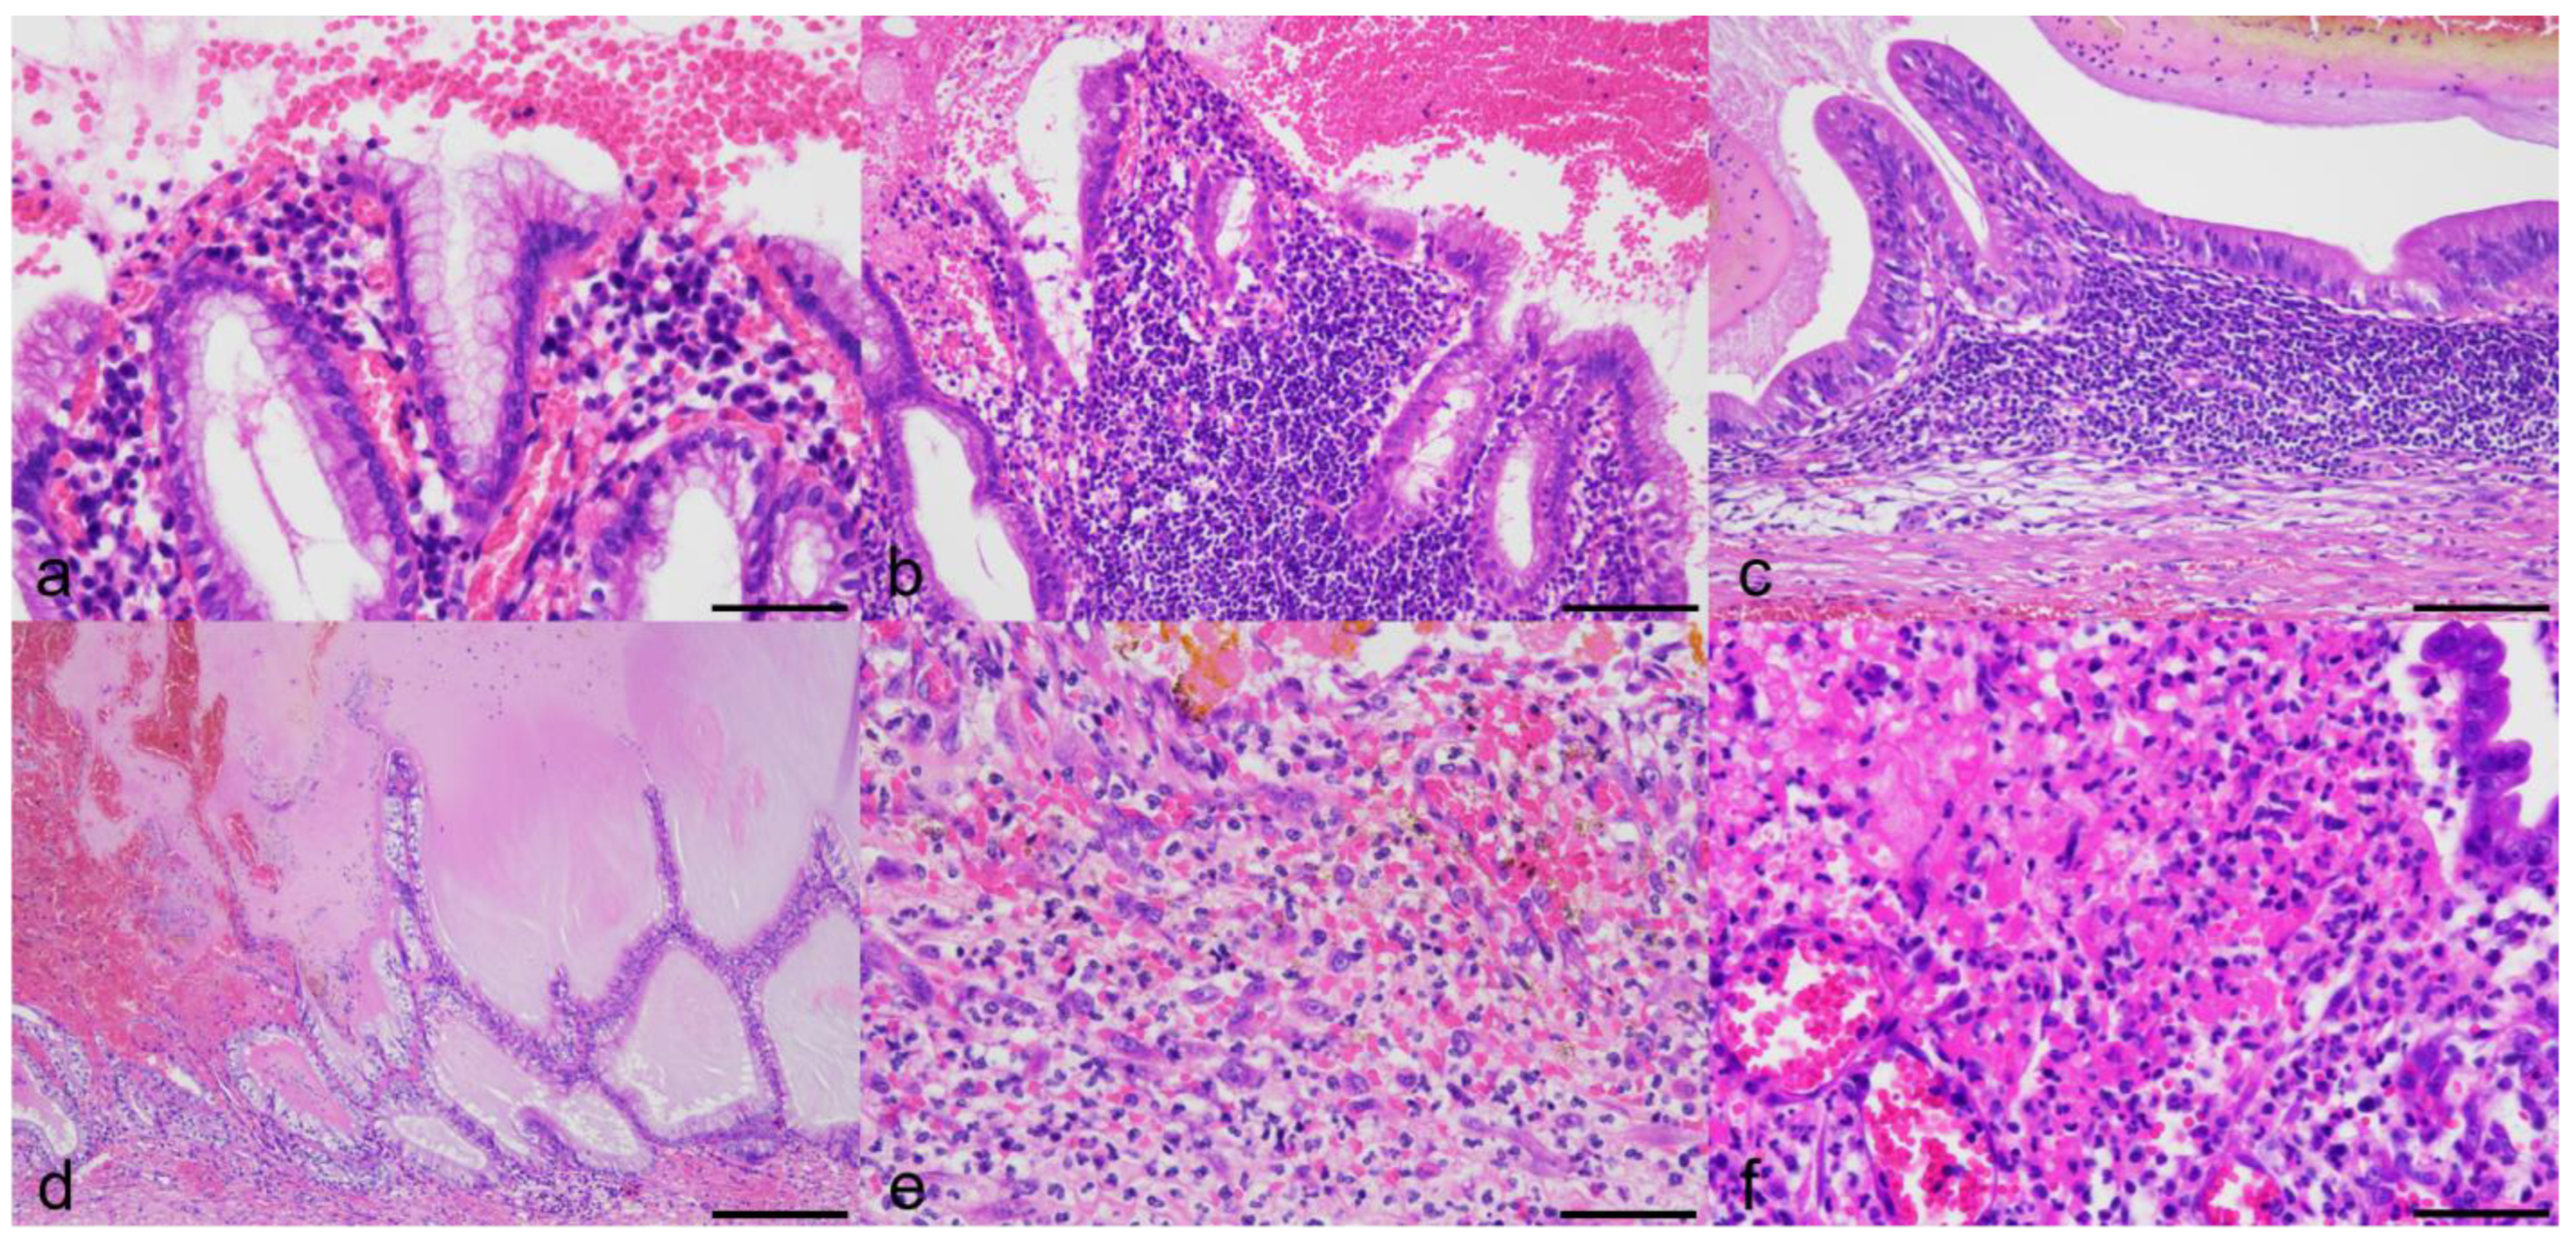

3.3. Histologic Findings